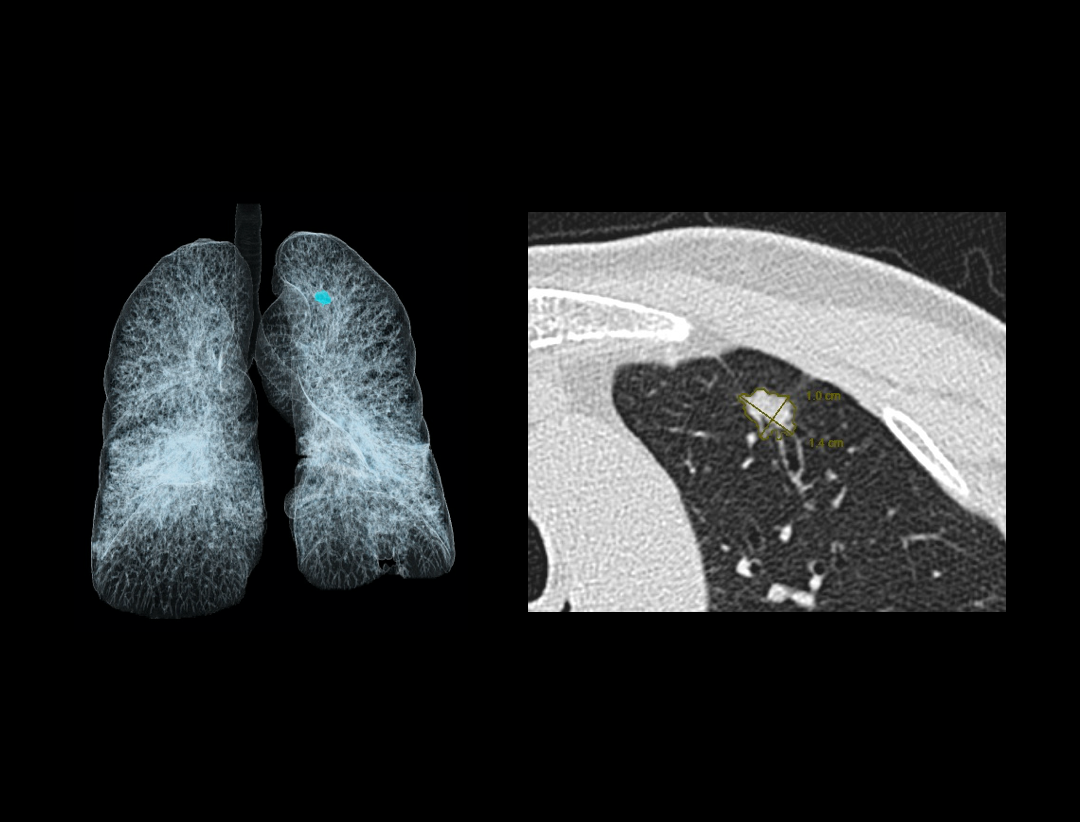

Pulmonary Nodule

Pulmonary Emphysema